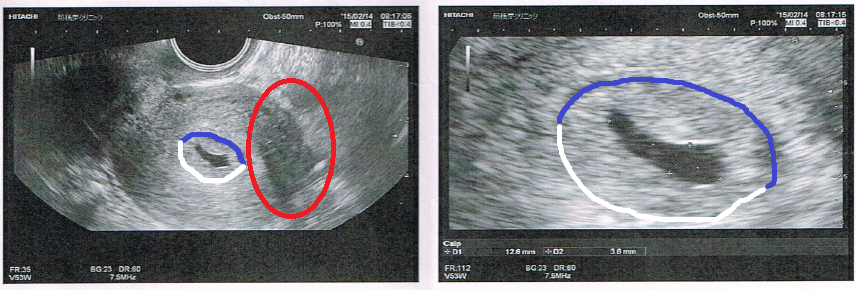

· bt17胎嚢確認診察。大きさやe2が平均値より低いのが気がかり。 18年3月21日 ホルモン補充移植周期bt22の「成長・ホルモン値評価」に行ってきました。 nacのプリントによると、週数は5w6d。 (bt22診察は、経過により診察なしの方もいるようです) 前回のbt17胎嚢確認で寺元先生が、 「次回心拍 · 平均5人が回答 50以上の診療科の医師 医師に相談する トップ カテゴリ一覧 妊娠・出産 高齢出産 5w1d,BT17の胎嚢の大きさについて close 無料公開について 会員限定Q&Aのうち、どなたでも医師回答を見られる直近14日間に投稿された相談です。 全250万件の本人認証済みの医師が答えるQ&Aは正常(平均27mm)と 流産(平均26mm)であまり違いが見られません。統計的にも違いなし。 つまり、5週0日までは胎嚢のサイズを気にする必要なし! 次に5週1日~6週0日(36日から42日)を見てください。 正常の平均mm、 流産の平均45mm。統計的にも違います。

胎嚢確認できて良かった という安心感はあったけれど、 なんとなく大きさが気になってネットで検索しちゃうとね、 女医先生は「順調」って言ってくれたけれど、 前も5W6Dで9.8mmの胎嚢が · BT17 胎嚢確認 5w1d まずは数値から↓ E2 2267 P4 06 βHCG この日、朝茶色い出血があり焦る。 茶色だけど出血は出血どきどきしながら病院へ行きました。 結果、HCGが驚きの伸びを見せてくれました! そして胎嚢も無事確認!サイズは58mmと小さめ。 ネットでいろいろ見てると大きさが心配になるものの、とりあえずホッとしました 出血については、茶色胎嚢は、62mmでした。 夢クリの基準値(BT17)が510mmとの事でしたので BT18の判定という事を考慮すると かなりギリギリの数値ではありますが (この時期胎嚢は1日1mm成長) 何とか基準値内はクリアしてくれました。 先生からは

BT17 胎嚢小さい? 妊娠週数だと5週1日です。 胎嚢は4ミリ。 と言われたので悪い予感がして、待合室で胎嚢の大きさを検索。 小さい明らかに小さい。 「胎嚢確認出来ましたね。 では次の診察は一週間後の~」 とまたサッサと話が進んでいくので、慌てて「胎嚢小さくないですか? 」と質問し胎嚢確認bt17/klc16 40歳「ドリー」の女の子ママ ︎育児生活ブログBT17 とくに症状なしです BT16の5w0d 胎嚢が見なかったので 普通の胎嚢のサイズを探してみました! それっぽい研究資料ををみつけたのでそこから 胎嚢の大きさ 4w2d →15mm